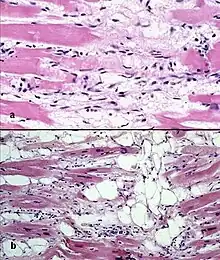

Typical micro-histologic features of ARVC/D. Ongoing myocyte death (upper) with early fibrosis and adipocyte infiltration (lower).

There are two pathological patterns seen in ACM, Fatty infiltration and fibro-fatty infiltration.

Fatty infiltration

At first, fatty infiltration, is confined to the right ventricle. This involves a partial or near-complete substitution of myocardium with fatty tissue without wall thinning. It involves predominantly the apical and infundibular regions of the RV. The left ventricle and ventricular septum are usually spared. No inflammatory infiltrates are seen in fatty infiltration. There is evidence of myocyte (myocardial cell) degeneration and death seen in 50% of cases of fatty infiltration.

Fibro-fatty infiltration

The second, fibro-fatty infiltration, involves replacement of myocytes with fibrofatty tissue. A patchy myocarditis is involved in up to 2/3 of cases, with inflammatory infiltrates (mostly T cells) seen on microscopy. Myocardial atrophy is due to injury and apoptosis. This leads to thinning of the RV free wall (to < 3 mm thickness) Myocytes are replaced with fibrofatty tissue. The regions preferentially involved include the RV inflow tract, the RV outflow tract, and the RV apex. However, the LV free wall may be involved in some cases. Involvement of the ventricular septum is rare. The areas involved are prone to aneurysm formation.

A biopsy sample that is consistent with ACM would have > 3% fat, >40% fibrous tissue, and <45% myocytes.

A post mortem histological demonstration of full thickness substitution of the RV myocardium by fatty or fibro-fatty tissue is consistent with ACM.